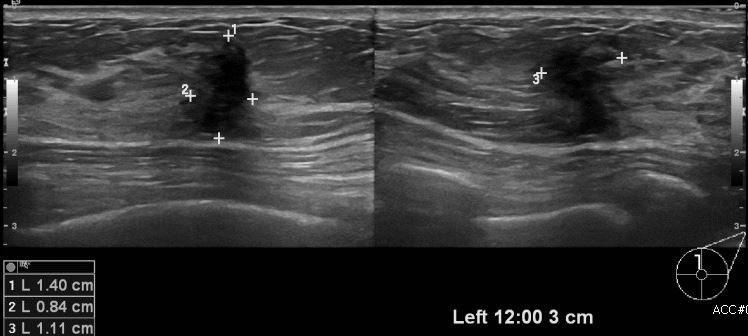

상기환자 건강검진상 이상 소견으로 내원하신 40대 여성분으로 좌측 12시 방향에서

3 cm 떨어진 거리의 혹 조직검사 시행하여 좌측 침윤성 유관암 진단 되었습니다.